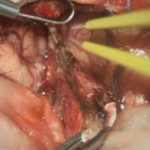

712

'25年12月

70代

下垂体腫瘍

頭蓋内腫瘍摘出術

No.’25_114 摘出 前

No.’25_114  摘出 中

No.’25_114 摘出 後